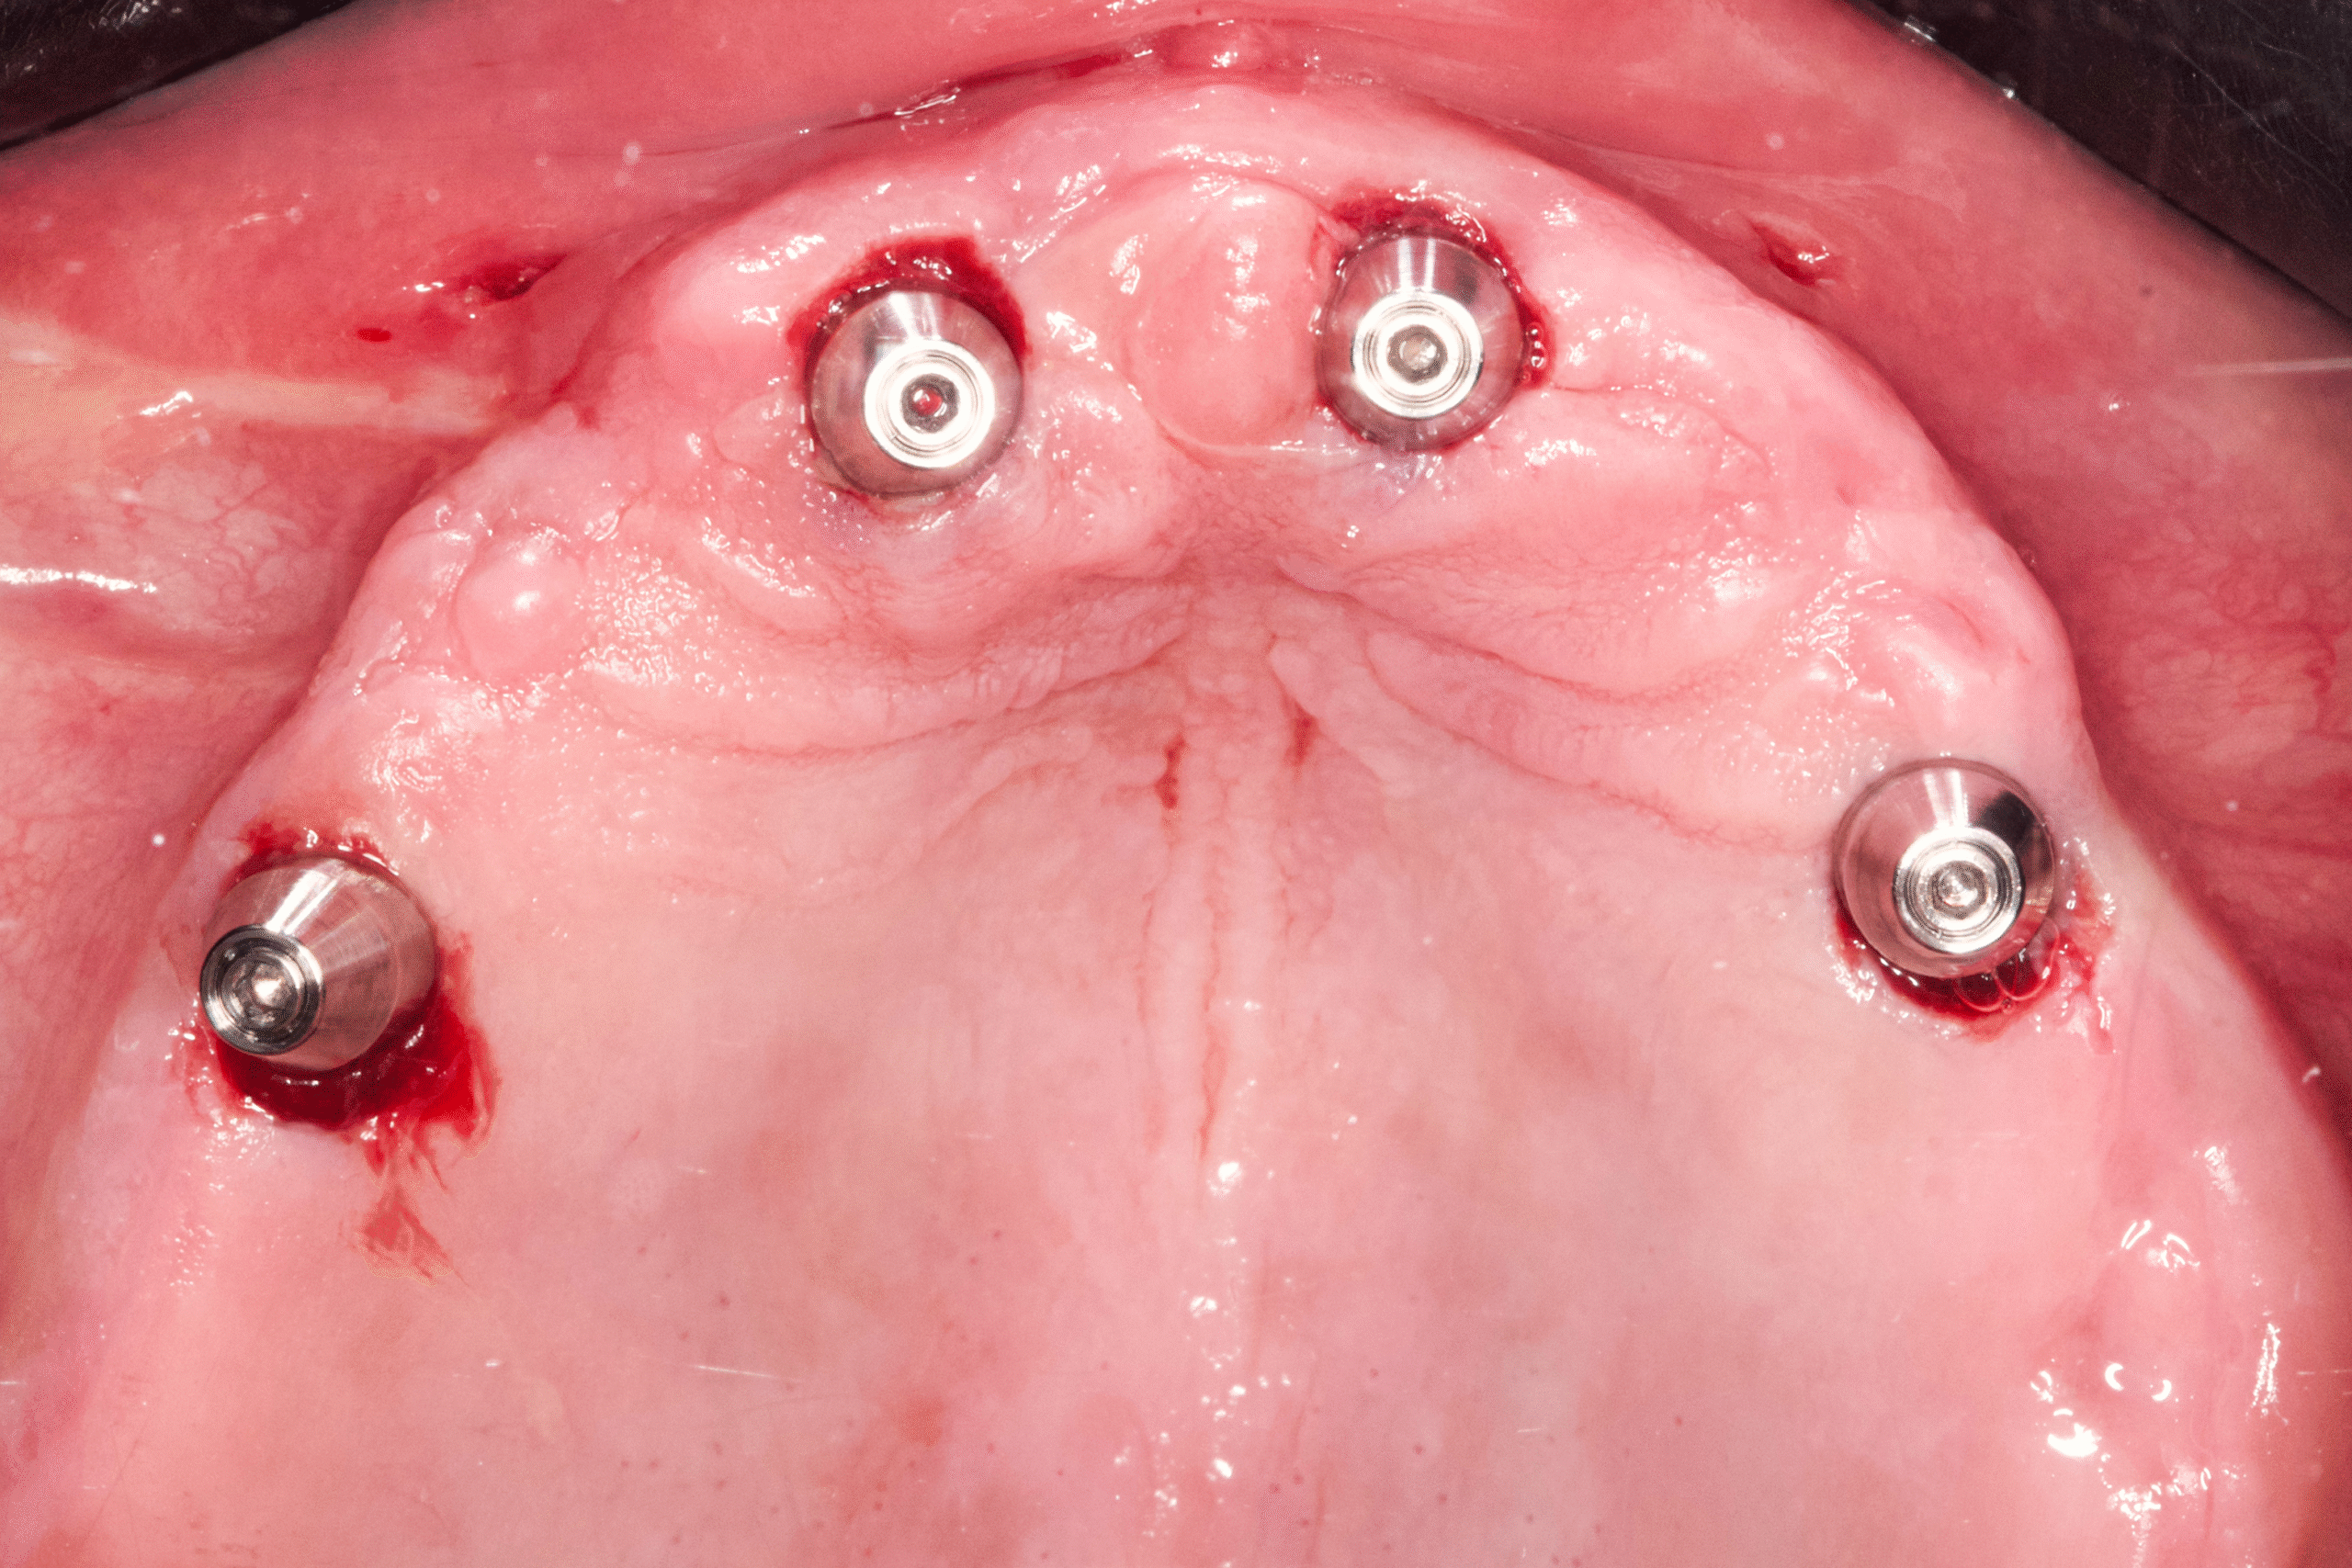

- Placement of multiple implants in the upper jaw

- No incisions, no sutures, minimal bleeding

In only 3 hours, James received a complete upper-jaw reconstruction and a corrected lower-arch restoration using a fully flapless implant technique.